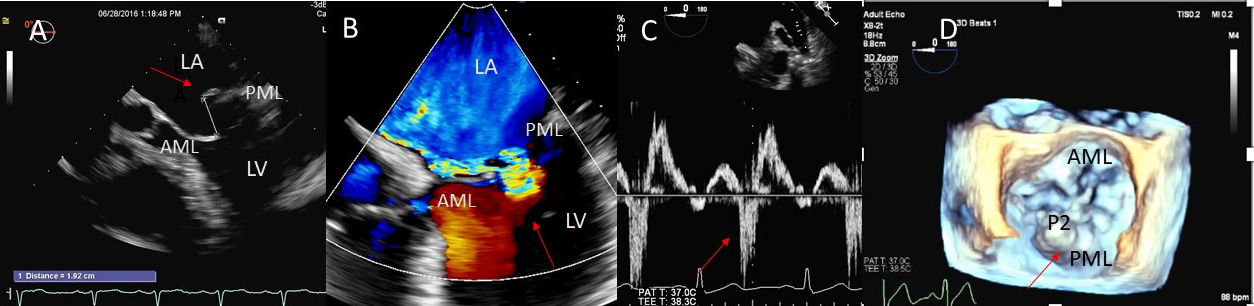

Fig. 1.Degenerative MR due to Flail posterior mitral valve leaflet. (A) TEE 4 chamber view showing a flail posterior mitral valve resulting in a severe anteriorly directed mitral regurgitation jet. LA, left atrium; LV, left ventricle; AML, anterior mitral leaflet; PML, posterior mitral leaflet. (B) TEE 4 chamber view color Doppler showing anteriorly directed mitral regurgitation with PISA (red arrow). AML, anterior mitral leaflet; AV, aortic valve. (C) Pulsed wave Doppler showing left upper pulmonary vein systolic flow reversal. (D) 3D TEE enface view of the mitral valve from the atrial perspective demonstrating P2 flail scallop with torn chordae. Aortic valve is a 9 o’clock position. AML, anterior mitral leaflet; PML, posterior mitral leaflet.

Besides prolapsing or flail scallops, MR jet may also originate between individual scallops. This occurs more commonly between the posterior leaflet through cleft like indentations that sometimes extend to the mitral annulus. This origin of MR can be very difficult to diagnose on 2D TTE or TEE (Fig. 2A–C). 3D color Doppler further assists in confirming jet origin at the site of suspected leaflet pathology/ies including presence of mitral valve cleft like indentation/s. Presence of calcification on the annulus and leaflets and in the subvalvular apparatus further assists surgeon in planning repair [21]. Visualization of the valve from the LV perspective adds further information on leaflet morphology, coaptation and regurgitant site/s particularly if jet originates from mitral valve clefts. Optimal visualization of the MR jets using real-time 3D TEE leads direct guidance for catheter movement and positioning of the implanted device(s) capturing the opposing sides of anterior and posterior mitral leaflet scallops during catheter based MV interventional procedures [22].

Fig. 2.Mitral leaflet Cleft. (A) TTE short axis at the mitral valve level showing posterior mitral cleft. (B, C) Isolated cleft within the P2 segment of the posterior leaflet (associated with mitral regurgitation) on 3D TEE and TTE short axis views. AML, anterior mitral leaflet; PML, posterior mitral leaflet.

As opposed to degenerative MR, mitral valve leaflets in secondary MR may be normal but MR results from leaflet mal-coaptation due to a dilated mitral annulus as in dilated cardiomyopathy or due to tenting of mitral leaflets due to LV infarct remodeling causing outward displacement of papillary muscles and tethering of chordae attached to these papillary muscles. Mal-coaptation may be along the entire mitral leaflet coaptation plane mostly in functional MR (Fig. 3A–C) or localized to some scallops commonly seen at the P3 scallop of the mitral valve in the presence of a remodeled infero-posterior myocardial infarction causing tethering of the chordae to P3 scallop (ischemic MR).

Fig. 3.Functional Mitral regurgitation. (A) Transesophageal echocardiogram biplane view shows a dilated LV with mitral valve coaptation point displaced into the LV and central MR jet. (B) 3D TEE showing central mitral leaflet malcoaptation (white asterisks). (C) 3D TEE surgical view of the mitral valve showing severe central mitral regurgitation. LA, left atrium; LV, left ventricle; AML, anterior mitral.